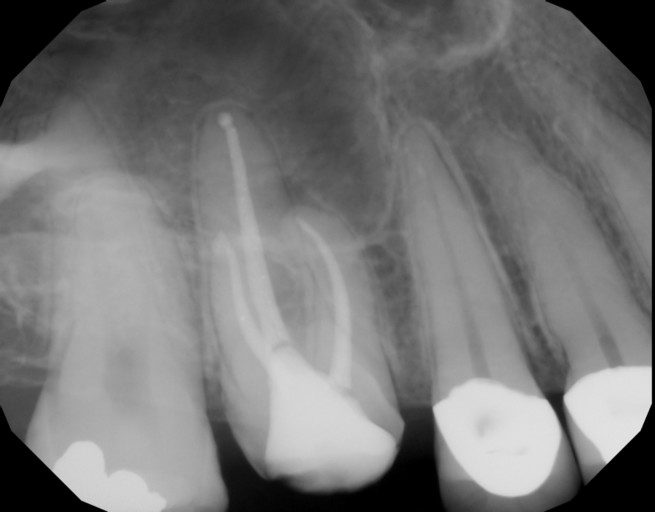

Is it possible to have a tooth thats infected for "a long time" but not need to be treated with an antibiotic? This dentist claims my friend needs a root canal and a crown(she's on medicaid) and medicaid doesn't cover either. they said she could have it pulled, but then it would be more expensive in the long run(probably because of the partial expense-pontic and retainer charge, I am guessing)... But they also said she could just leave it and do nothing for now.As far as I know people still die from tooth infections getting out of control and going to the heart and brain. it seems reckless or at the other end like they are full of it. More details -> my girlfriend is 35, and thats who I am asking for. she feels pain when drinking or eating cold foods. she has a big filling there already. which I figured there must be a spot there where the filling is not sealed properly.

Anytime anyone has a infection in the mouth from a tooth, usually needs antibiotic. As you mentioned that your girlfriend is on medicaid, which they do not cover dental. I suggest that she has the tooth removed and later when you could afford a partial denture you can do it. You did not mention which tooth, so its difficult to determine what to do. But she should be on anitbiotic. As the infection is not good for our body to fight. If you leave it alone, it will come back. As far as what the dentist said about a root canal and then a crown later. The nerve in that tooth is dying or died and that causes infection if not treated.